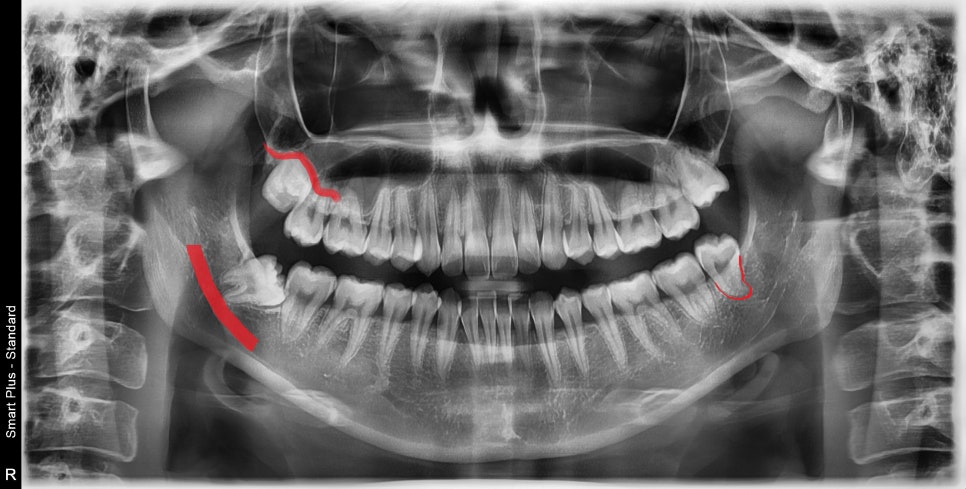

양쪽 위, 아래 4개의 사랑니가 모두 존재합니다.

한쪽은 적당히 맹출이 되어 어렵지 않게 뽑을 수 있습니다.

하지만 반대편은 모두 완전매복되어있는 사랑니이며

심지어 누워서 옆 치아를 누르고 있었습니다.

사랑니 발치를 할 때 치과의사가 고려하는 점은

치아의 매복 위치, 신경관과의 거리, 뿌리의 휨 정도, 치아를 감싸는 치조골 형태 등

여러 가지 조건을 보며 발치 계획을 세우게 됩니다.

매복치 위치 평가를 위해 3D CT를 찍고 분석을 해봅니다.

아래쪽의 매복 사랑니는 신경관과 근접해 있고, 뿌리가 살짝 휘어있지만

발치에는 큰 문제는 없어 보입니다.

하지만, 발치 과정에서 잇몸 절개와 주변 골삭제는 최소 필요해 보입니다.